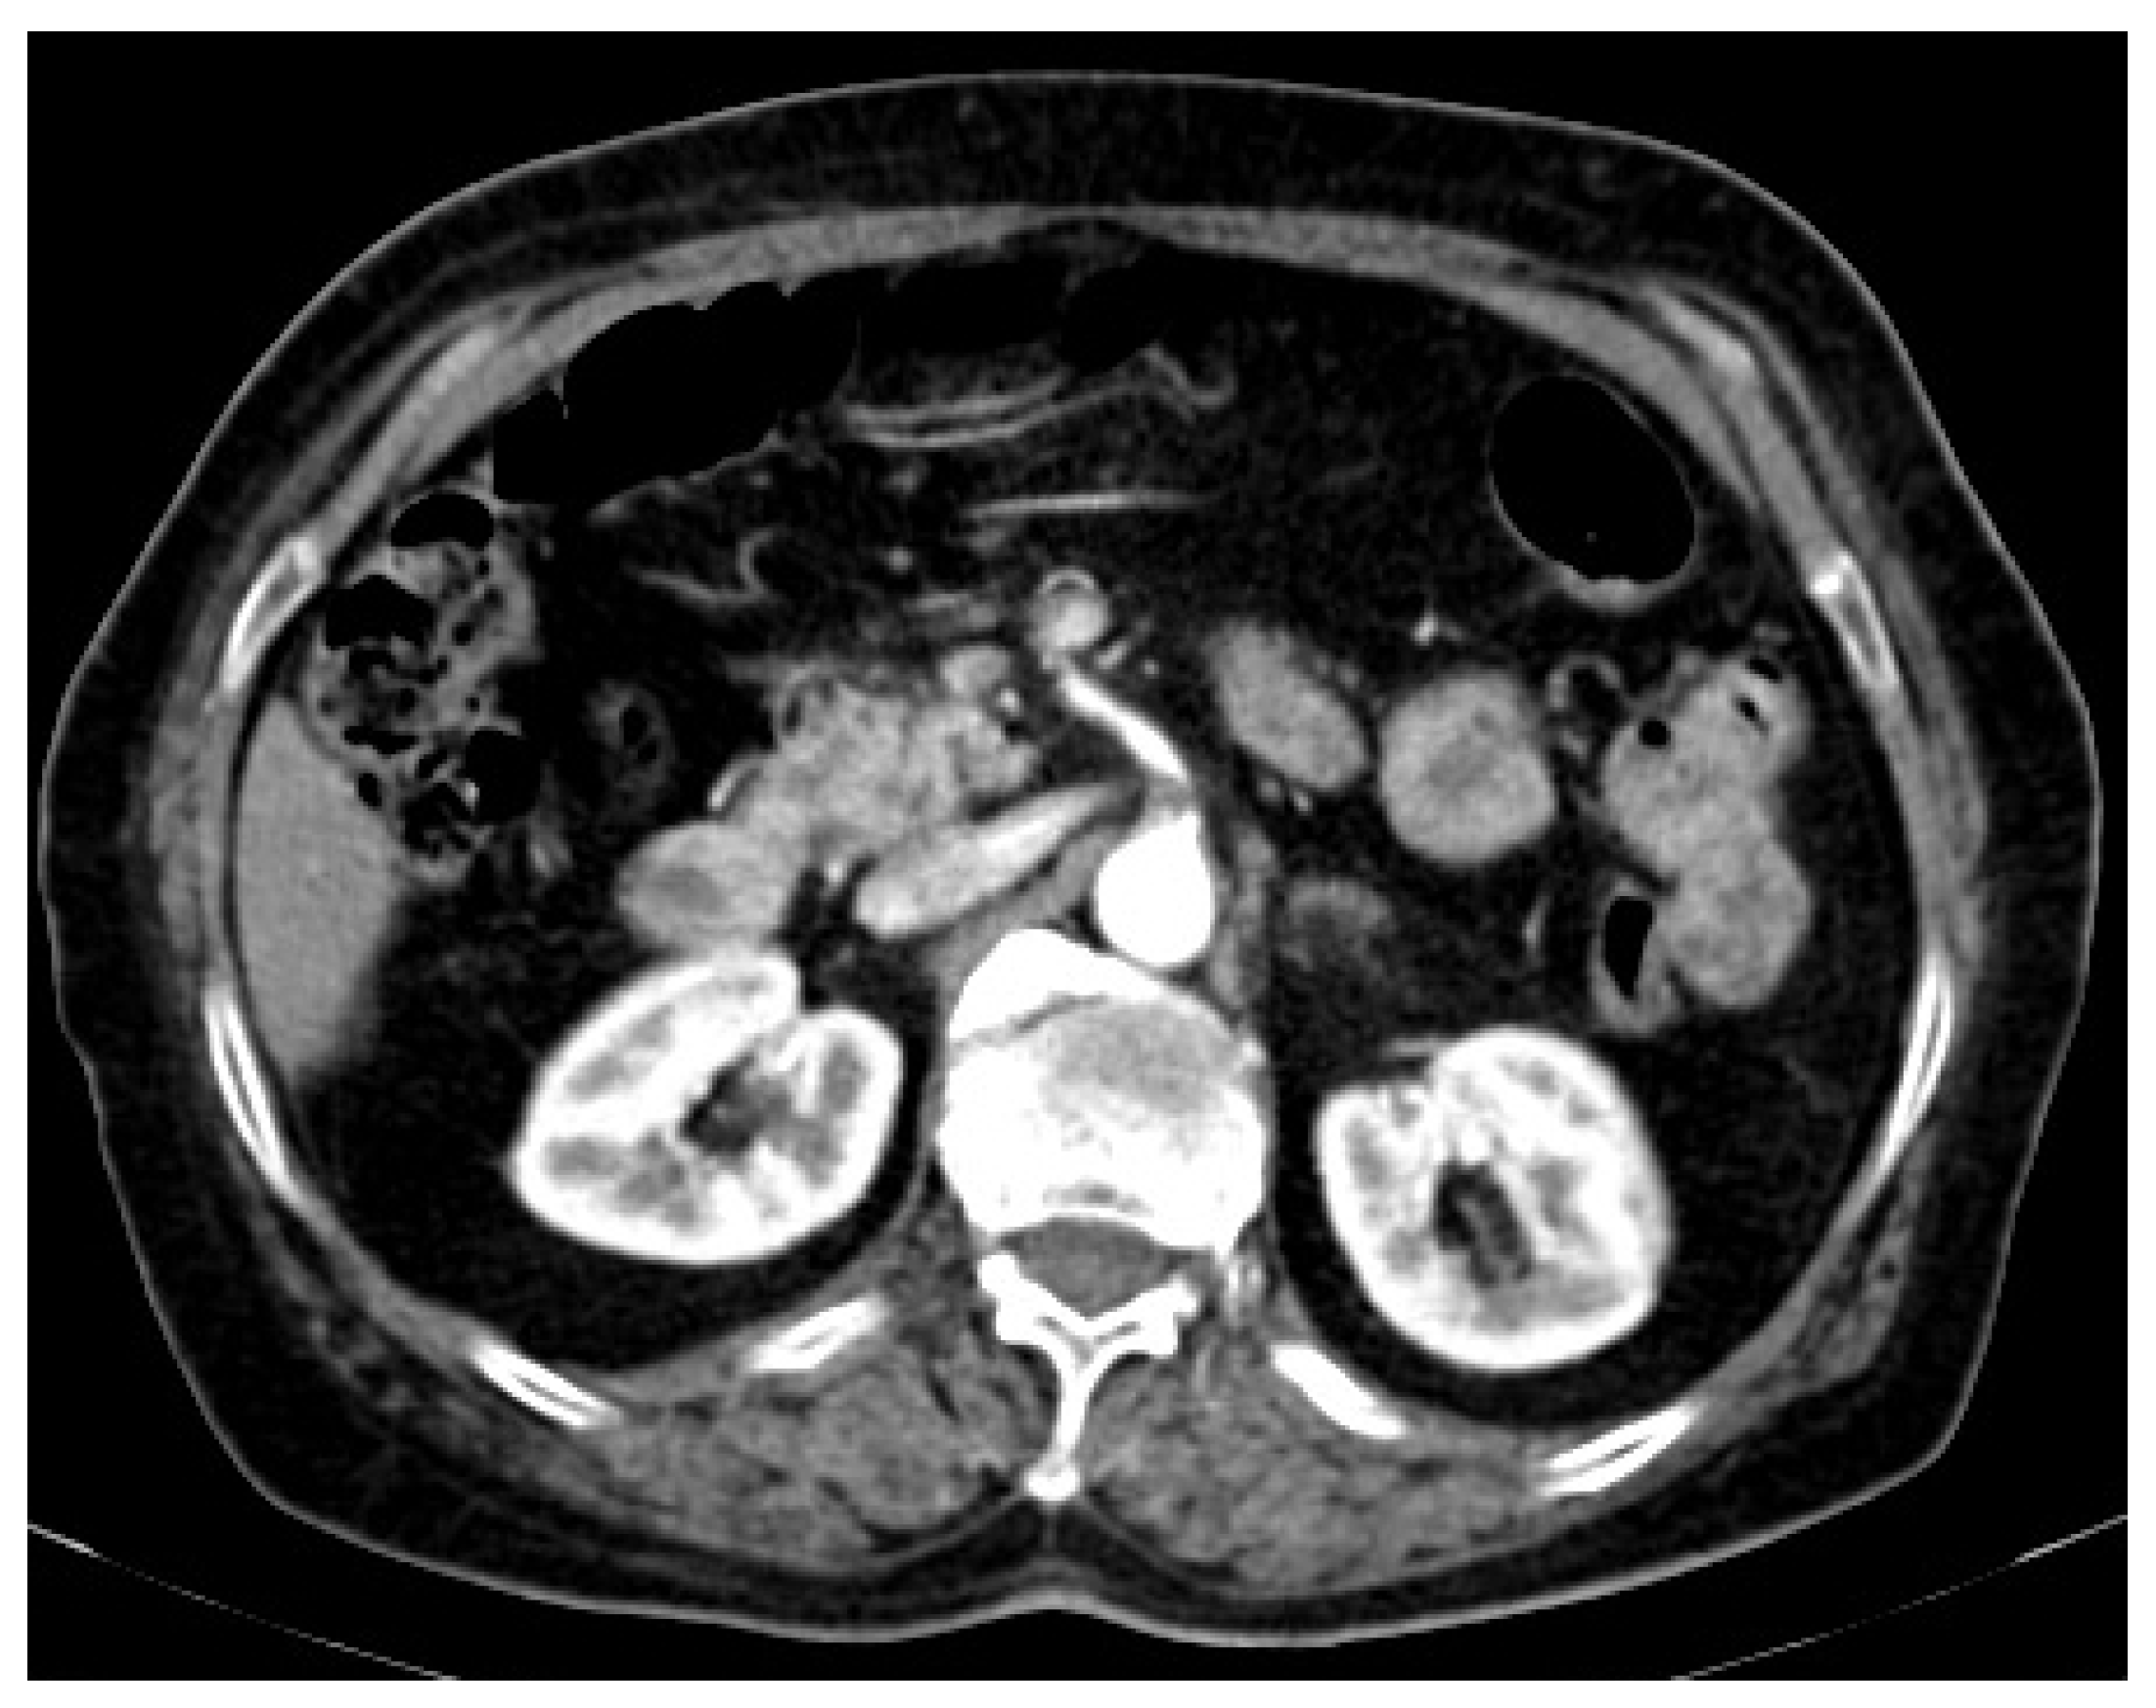

2. Case Presentation